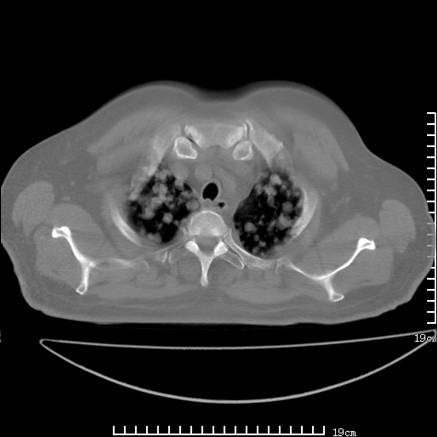

张男,75岁,干咳半年余,小便不利二年,b超检查前列腺增大,未见明显肿块;前列腺癌血生化检查多项指标明显增高。

双肺内多发转移瘤,纵膈淋巴结转移。来源前列腺?建议盆腔mri进一步检查。

双肺转移满了。

两肺广泛转移瘤。